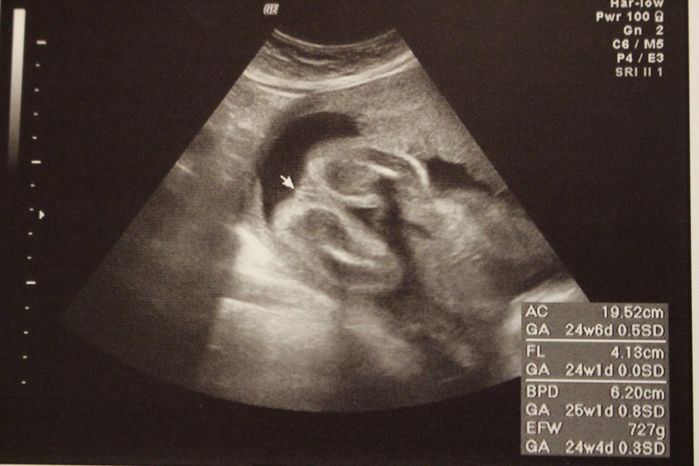

妊娠24週目のエコー写真

2D画像。医師から「今、性別を知りたいですか?それとも楽しみに取っておきますか?」と尋ねられ、名付けや準備に必要だからと教えてもらいました。前夜にみた夢のお告げ通りだったので、ますます神秘的な気持ちになりました。